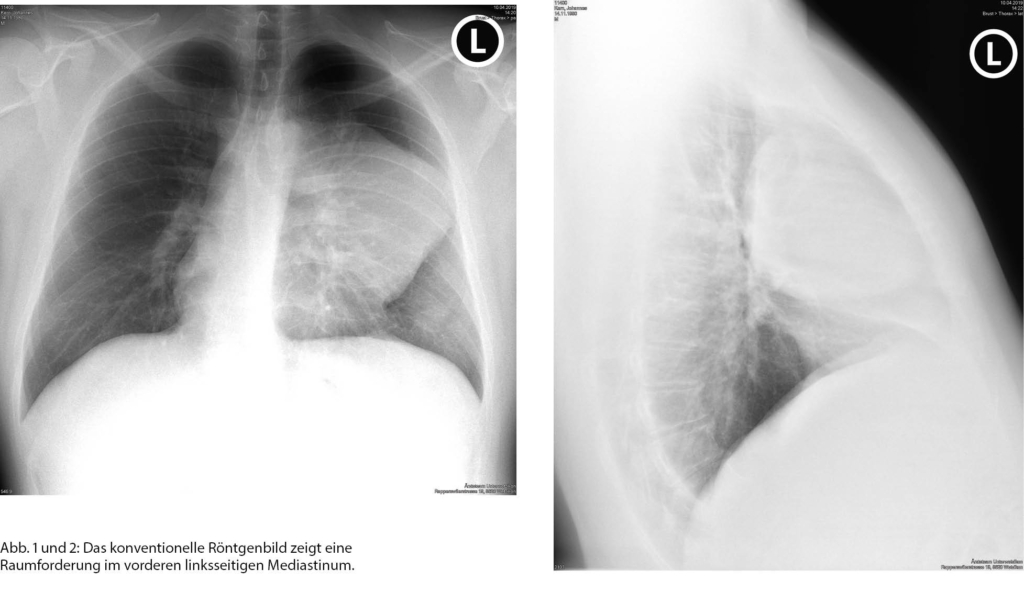

In diesem Fall konnte bereits aus der Tumorlokalisation im vorderen Mediastinum die radiologische Differenzialdiagnose in diesem Bereich auf die 5T: teratoma, thymoma, thyroidea, terrible lymphoma, tortuous vessels) eingegrenzt werden (Tabelle 1).